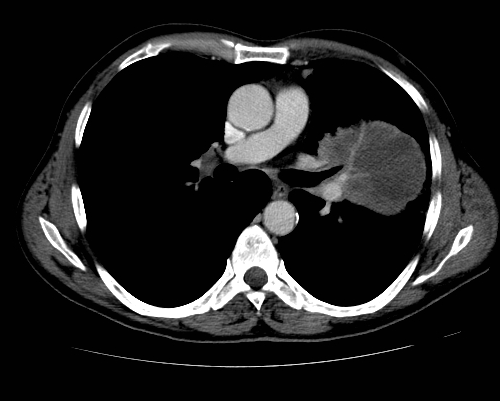

Figure B: CT of Central Pulmonary Artery Invasion.

Many patients with tumors involving the central airways will also have involvement of central vascular structures, with an estimated incidence of combined involvement of 13% to 80%.[43-45] Surgical resection of tumors with vascular invasion is often an option for patients with limited involvement of the superior vena cava (SVC) or pulmonary artery (PA) (Figure B). Resection of tumors with invasion of the subclavian vessels is considered for Pancoast tumors involving these vessels. PA resections are limited to tumors involving < 1–1.5 cm of the intrapericardial PA in order to obtain negative margins and avoid cardiopulmonary bypass. PA sleeve resections and vascular reconstruction can also allow distal parenchymal preservation for tumors involving the PA in the hilum or fissure. Five-year survival for vascular sleeve resections involving the SVC or PA ranges from 29% to 52% and is highly influenced by the presence of mediastinal nodal disease.[44-48] Under most circumstances, central vascular involvement that requires the use of cardiopulmonary bypass should be considered a contraindication for resection. Likewise, tumors involving the aorta are rarely amenable to resection, although there are published reports of segmental excisions with partial cardiopulmonary bypass support or excision of tumors with aortic arch involvement that is performed with the patient under hypothermic circulatory arrest.[49,50]